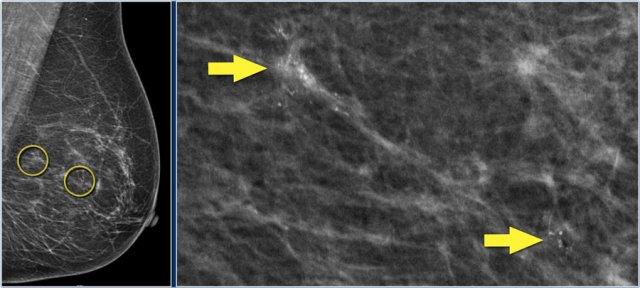

Dưới đây là ví dụ về một bệnh nhân ung thư vú giai đoạn tiến xa.

Siêu âm tuyến vú phát hiện tổn thương giảm âm kích thước 18mm với bờ không đều và vôi hóa vi thể.

Siêu âm nách phát hiện một hạch bạch huyết không còn rốn hạch mỡ.

Chọc hút tế bào bằng kim nhỏ (FNA) được thực hiện, và cả khối u lẫn hạch bạch huyết đều dương tính với adenocarcinoma.

Tổn thương được phân giai đoạn lâm sàng là cT1N+. PET-CT được thực hiện tiếp theo.

Trên hình PET-CT phía trên, một hạch bạch huyết mức độ II dương tính nằm ngay bên dưới cơ ngực bé (mũi tên vàng).

Nhiều hạch nách được phát hiện nhưng không có di căn toàn thân.

Mô mỡ nâu bình thường được nhìn thấy dọc theo cơ cổ và cơ vai ở cả hai bên (vòng tròn).

Bệnh nhân này được lên kế hoạch điều trị tân bổ trợ và sinh thiết được thực hiện để xác định độ mô học, thụ thể nội tiết và khuếch đại HER-2-neu.